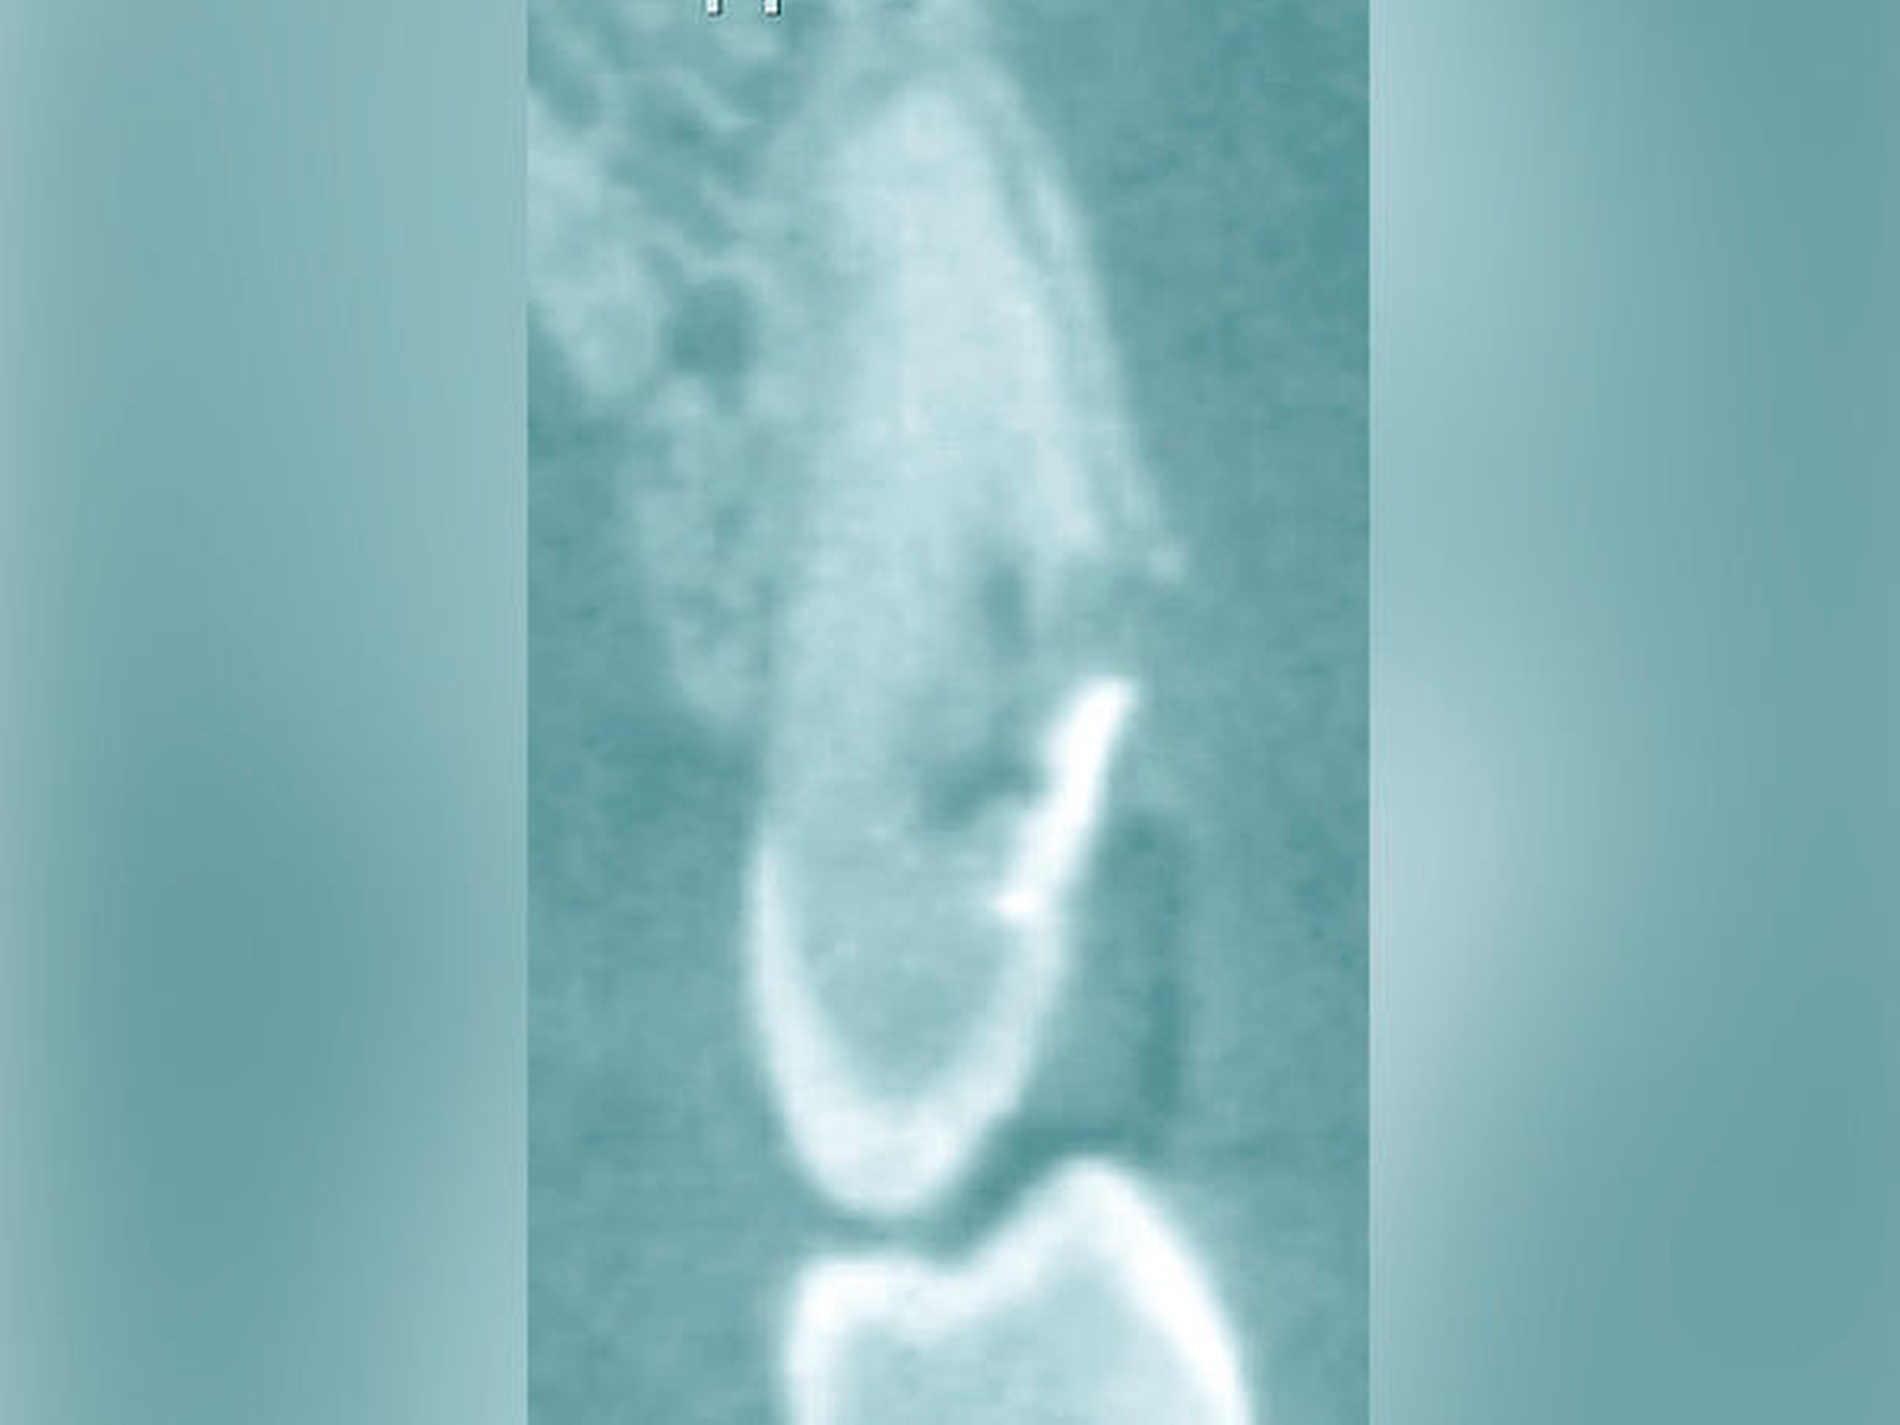

Eine weitere Möglichkeit, tief zerstörte Zähne möglichst schonend chirurgisch zu extrudieren, basiert auf axialen Zugsystemen (Abbildungen 2 bis 4). Diese erscheinen vorteilhaft bei sehr schwierigen Fällen, zum Beispiel bei Zähnen mit fehlendem Ansatzpunkt für die Zange sowie bei langen oder sehr ovalen Wurzeln. Axiale Zugsysteme ermöglichen die Übertragung von Zugkräften auf die Zahnwurzel, ohne die Alveole unnötig zu dehnen. Dazu wird eine spezielle Schraube in den Wurzelkanal eingebracht und das Gewinde der Schraube für eine ausreichende Friktion fingerfest eingedreht. An diese Schraube wird ein gerätespezifisches Zugsystem angelegt. Durch rein axial wirkende Zugkräfte werden traumatische Effekte auf Knochen und Wurzeloberfläche während der Zahnmobilisation minimiert. Gegebenenfalls können feine Luxatoren vorsichtig unterstützend eingesetzt werden. Im Tiermodell wurde an extrahierten und wieder replantierten Zähnen mit ovalem Querschnitt gezeigt, dass der Verlust von Zementoblasten auf der Wurzeloberfläche geringer ist, wenn ein axiales Zugsystem anstatt einer Extraktionszange verwendet wird.

Die wesentliche technische Komplikation stellt das unverhältnismäßige Erweitern des Wurzelkanals für die Retention des Zughilfsmittels – zum Beispiel der Benex-Schraube – dar. Der Behandler sollte hier unter besonderer Vorsicht den bereits instrumentierten und präparierten (vorgegebenen) Wurzelkanal als Bohr- und Zugpfad für die Extrusion nutzen. Auf die Schonung der gesunden Zahnhartsubstanz muss geachtet werden. Die Bohrachse für die Ausrichtung der Zugschraube muss mit dem koronal gelegenen Hauptpfad des Wurzelkanals übereinstimmen. Zudem ist für das Erzielen einer ausreichenden Retention der Schraube ein gewisses Maß an Feingefühl und Taktilität vom Behandler erforderlich. Eine neue Schraube erfüllt die Vorbedingung eines schneidfreudigen Gewindes und damit eines guten Halts im Zahn am besten.